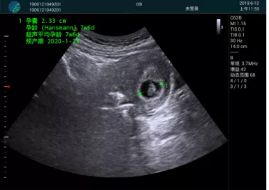

清晰顯示孕囊,通過軟件包計算孕齡7w+6d

M20實時引導,術(shù)中清晰顯示孕囊被破壞和抽吸針的過程,清晰顯示吸引針

抽吸結(jié)束后縱切子宮,孕囊已被完全抽吸,未見明顯殘留